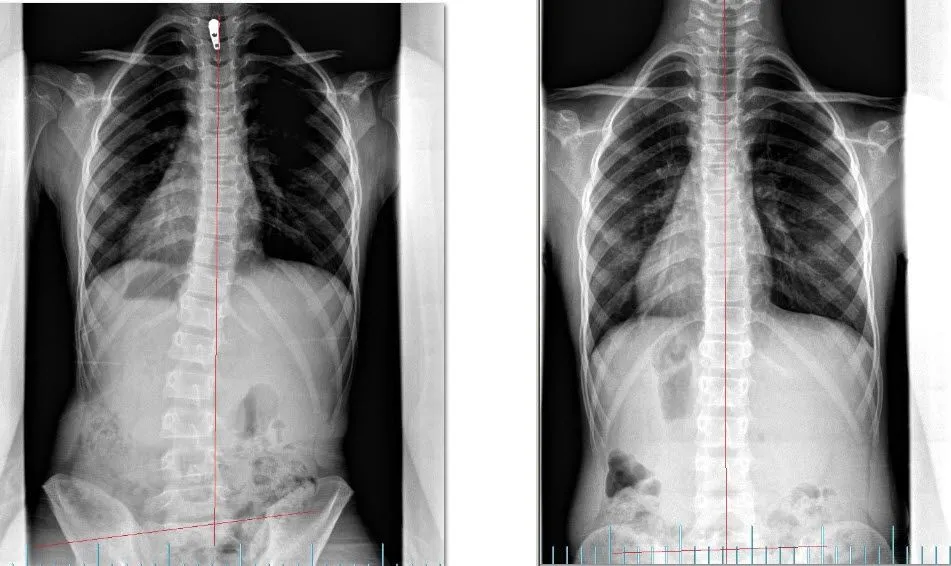

When the spine is well aligned, there is little to no nerve stress and the body is able to function optimally. Some times through physicals stresses such as motor vehicle accidents, slips and falls, sports injuries, and other traumas.  The spine can get misaligned and put pressure on the nervous system affecting the way that the body functions. Our job as doctors is to find out where the interference is and reduce it through Chiropractic Adjustments.  Objectively we can document where the problem is and then measure our patients progress as they go through the rehabilitation process.  Below is a series of before and after X-Rays of some our patients.

BEFORE AFTER

SCOLIOSIS CORRECTION